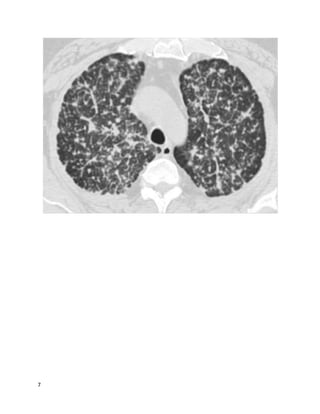

Question 17 of 82 (score?)

You are consulted by the ED for 40-year-old man presenting with shortness of

breath and dry cough. He supervises construction and has been on-site for

excavations in Tennessee, Ohio, Arizona, and Alabama, all in the last 2 months.

He was diagnosed with pneumonia at an urgent care center 2 weeks ago and

treated with levofloxacin for 1 week, with no improvement. Then he was

prescribed prednisone 20 mg daily for 1 week, with steady worsening of his cough

and subjective fevers.

His temperature is 101, pulse 105, respirations 20, blood pressure 125/85. Oxygen

saturation is 94% on room air. White blood cell count is 13,000 with 25%

eosinophils. A chest X-ray shows patchy multifocal pneumonia.

You schedule him for bronchoscopy. What do you most strongly recommend the

In this patient with a pneumonia that has been unresponsive to broad-spectrum

antibiotics and a courseof corticosteroids, with travel & exposure history

suspicious for fungal infection, empiric antifungal therapy should be provided.

37

Coccidioides is the only dimorphic fungus that causes peripheral eosinophilia.

Itraconazole or fluconazole are the preferred treatments for non-life-threatening

coccidioidomycosis, with amphotericin B reserved for severe or disseminated

infections. These agents are also effective treatment for histoplasmosis and

blastomycosis (with ampho-B reserved for severe infections). There is insufficient

data to supportthe use of voriconazole or posaconazole.